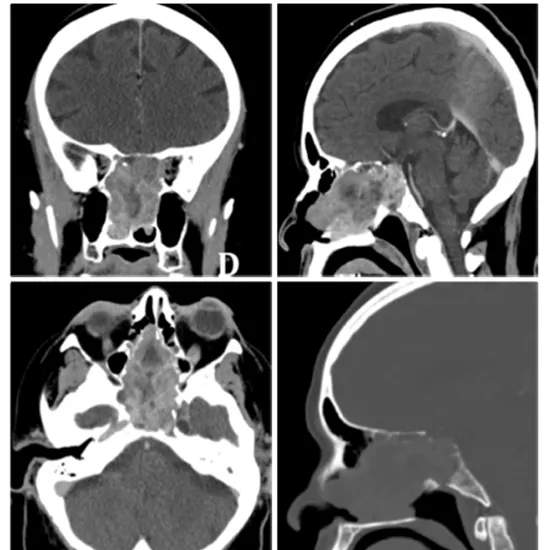

CECT Pituitary Gland Computed Tomography is a contrast-enhanced computed tomography of the pituitary gland. It is a type of imaging scan that employs X-ray beams and contrast media to produce cross-sectional images of the pituitary gland. The pituitary gland is a bony nook gland at the base of the skull. This scan assists doctors in diagnosing pituitary gland abnormalities such as pituitary gland shrinkage, the presence of tumours, and other problems affecting the gland.

Doctors prescribe CECT Pituitary Gland To detect the problems in the pituitary gland such as shrinkage, flattening of the pituitary gland, the presence of tumours in the pituitary gland, and the root cause of hemianopsia.